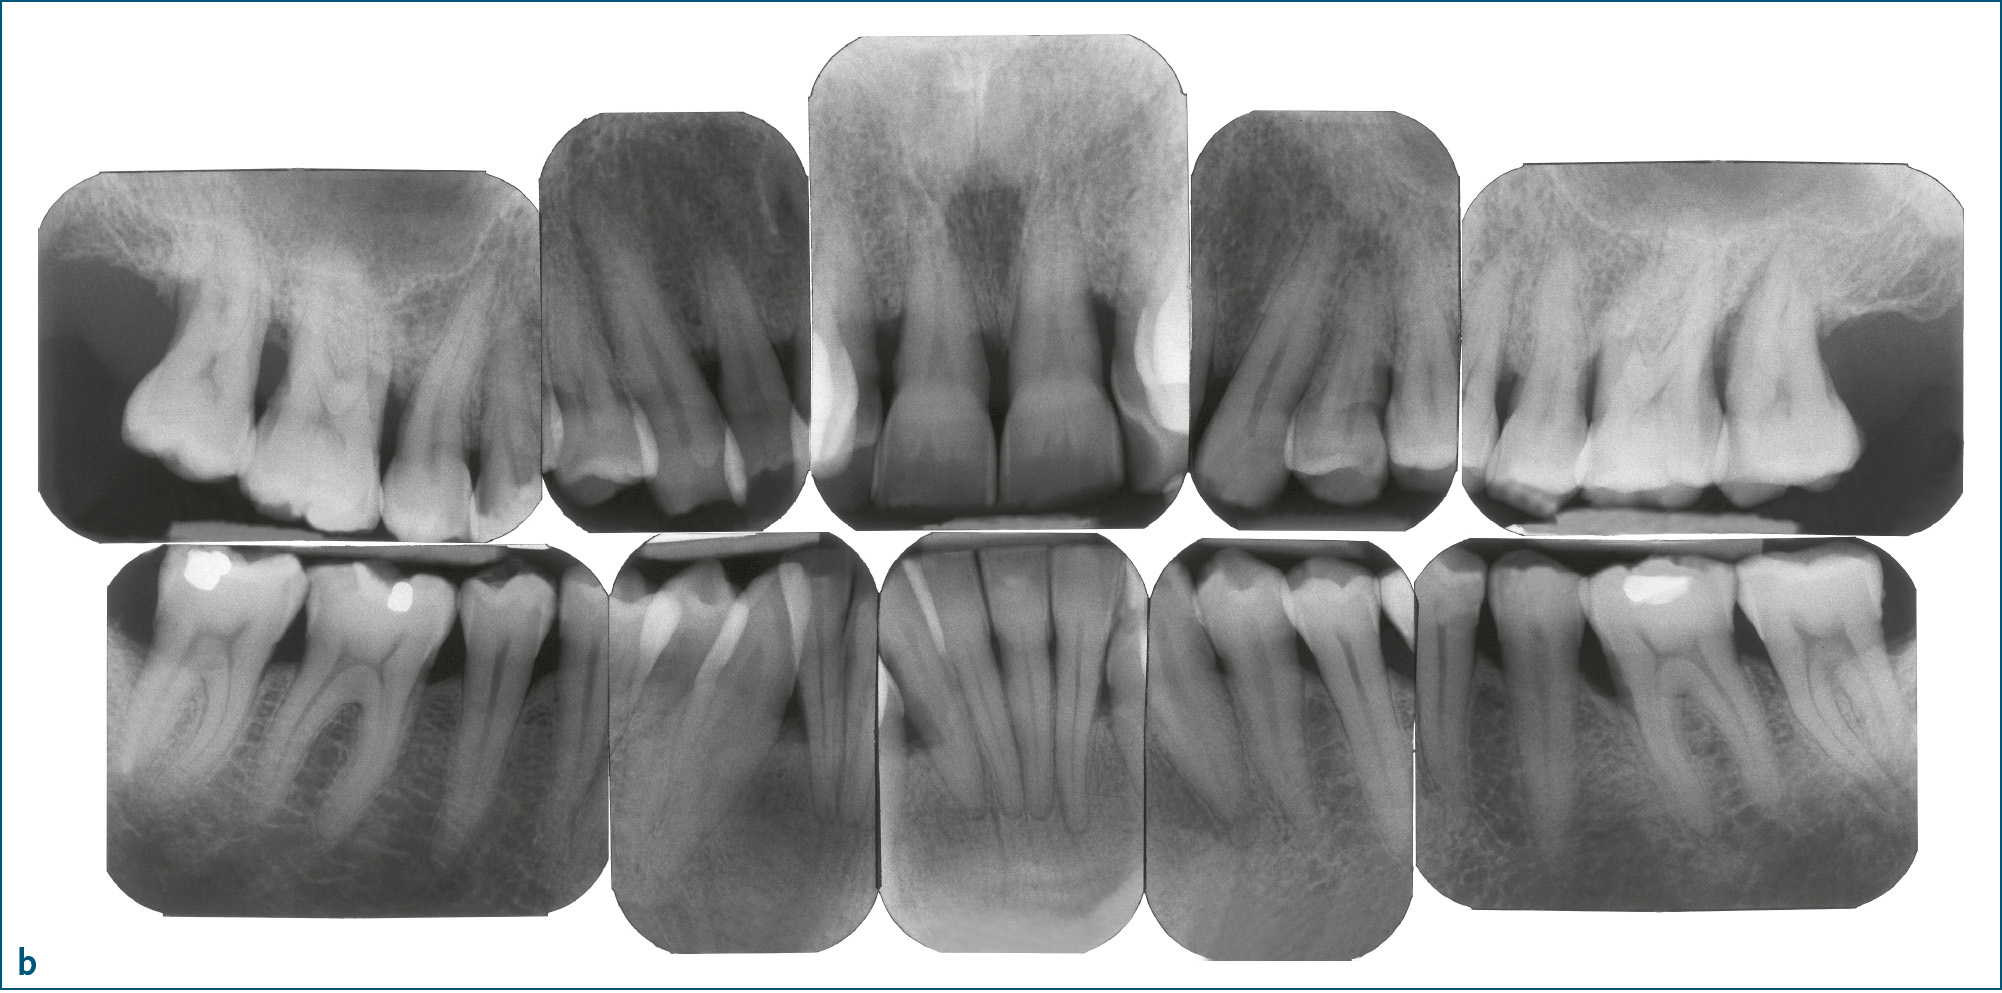

Abb. 1a bis d Parodontitis: a) Mann im Alter von 52 Jahren, Parodontitis, generalisiertes Stadium III, Grad C10: klinische Ansicht (Zahnfehlstellungen im Ober- und Unterkieferfrontzahnbereich, 31 Zahnstein); b) Röntgenstatus zu Abb. 1a: generalisierter überwiegend horizontaler Knochenabbau unterschiedlichen Ausmaßes (bis ins koronale Wurzeldrittel: 15–13, 23, 37–33, 43–47 [bis 33 % der Wurzellänge]; mittlere Wurzeldrittel: 17, 16, 12–22, 24–27, 32–42 [> 33 % der Wurzellänge]; auch am gleichen Zahn (z. B. 36); c) Frau im Alter von 24 Jahren: Parodontitis, generalisiert Stadium III, Grad C10; d) Panoramaschichtaufnahme zu Abb. 1c: Während sich an den Seitenzähnen des 2. Quadranten praktisch kein Knochenabbau findet, weisen andere Zähne Knochenabbau bis ins apikale Wurzeldrittel auf (z. B. 13, 33).